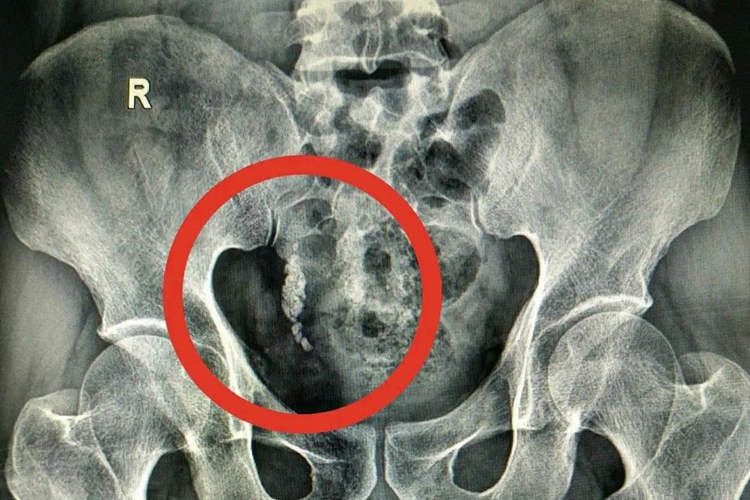

当机体右侧输尿管下段出现结石时,影像学检查结果表现为局部出现类圆形致密的结石影,同时患者可伴随血尿、尿痛等现象。

右侧输尿管下段结石,通过影像学检查可发现局部走行区内,出现强回声灶伴后方声影,也可能出现类圆形致密影或结石影。此外,患者多可伴随典型的肾绞痛和镜下血尿现象,疼痛可向大腿内侧,或阴唇放射。常伴有恶心、呕吐,严重时,血尿为肉眼可见。